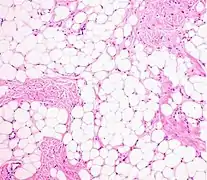

التشريح المرضي للورم الشحمي: تتكون الكتلة من فصيصات من الأنسجة الدهنية البيضاء الناضجة مقسومة على حاجز ليفي يحتوي على أوعية رقيقة الحجم ذات جدران شعيرية. [15]